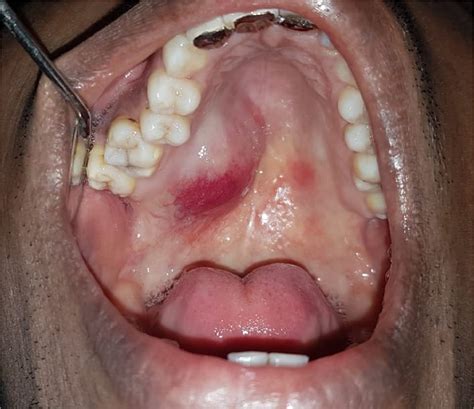

Discovering a nodule in roof of mouth can be a source of significant anxiety. The oral cavity is a complex environment, and while most bumps or lumps found on the palate are benign, they often cause immediate concern due to their proximity to sensitive areas. Whether you are feeling a small, painless bump while brushing your teeth or experiencing discomfort while eating, it is essential to understand the potential causes, symptoms, and when it is time to seek professional medical advice. By breaking down the anatomy of the palate and the common conditions that affect it, we can better navigate the process of diagnosis and management.

The roof of the mouth, known medically as the palate, consists of two distinct parts: the hard palate at the front and the soft palate at the back. Because the tissue here is tight against the underlying bone in the hard palate, any swelling or growth—such as a nodule in roof of mouth—often becomes noticeable very quickly. This tissue is subject to daily wear and tear from hot foods, sharp textures, and oral hygiene habits, making it prone to various irritations and minor injuries.

Common Causes of a Nodule in Roof of Mouth

There are several reasons why a bump might appear on your palate. Understanding these can help you distinguish between a temporary irritation and something that requires a dentist’s intervention.

• Torus Palatinus: This is a very common, painless, bony growth that occurs in the center of the hard palate. It is benign and often grows so slowly that people do not notice it for years.

• Oral Mucocele: These are fluid-filled sacs that occur when a minor salivary gland duct becomes obstructed. They often appear as clear or bluish bumps.

• Fibromas: These are smooth, pink, and firm bumps caused by chronic irritation, such as biting the roof of your mouth or constant rubbing from food.

• Cysts: Various types of cysts, such as nasopalatine duct cysts, can develop behind the front teeth and manifest as a nodule in roof of mouth.

• Abscesses: Often resulting from a dental infection or a localized tooth problem, an abscess can cause a painful, red, and swollen bump.